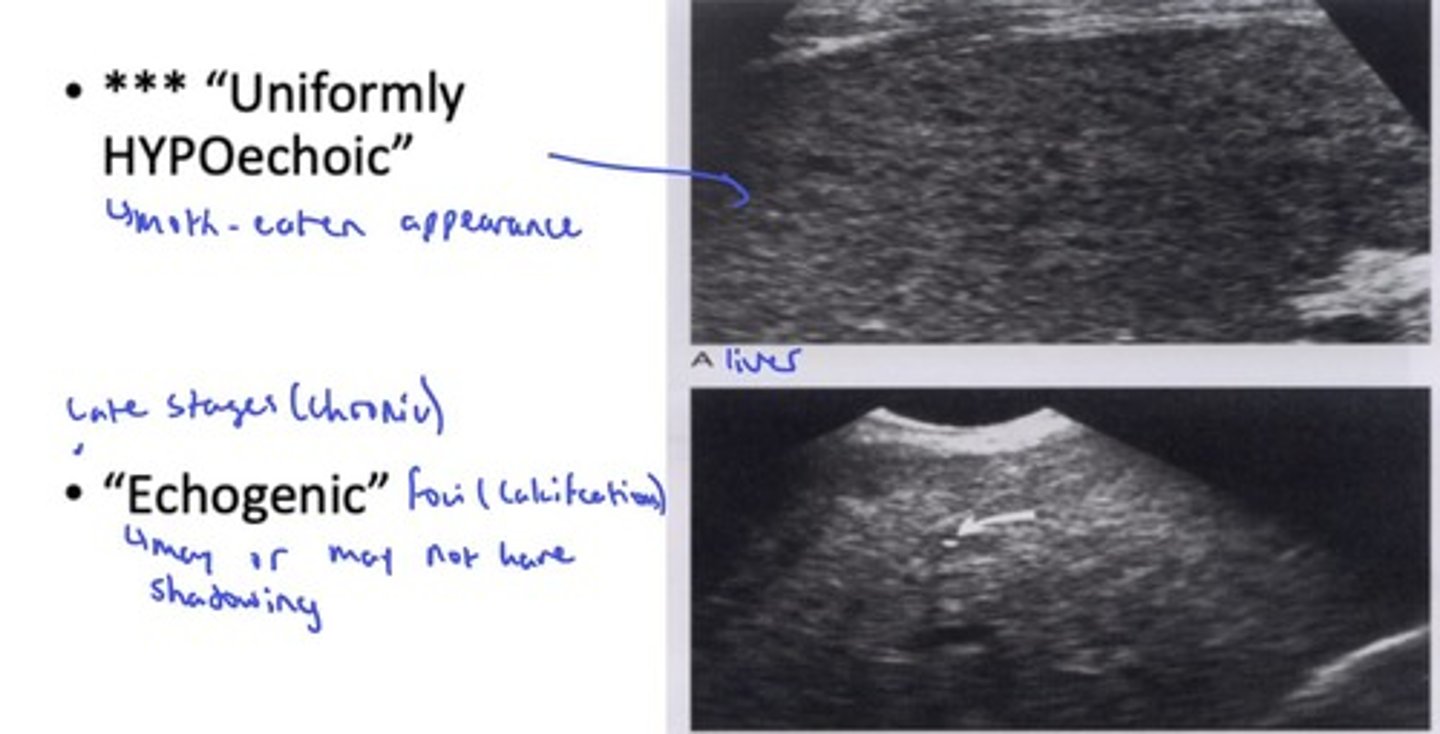

What are the sonographic features of candidiasis? (HINT: 4)

- Early stages: wheel within a wheel, bull's eye (1-4cm); Hyperechoic centre, hypoechoic rim

- Uniformly hypoechoic (moth-eaten appearance)

- Late/chronic: echogenic foci (calcifications w/ or w/o shadowing)

- Microabscesses: multiple small hypoechoic